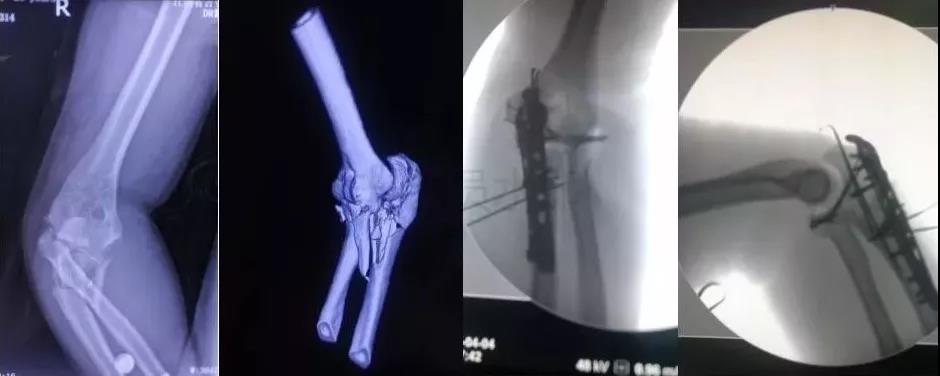

3)肱骨远端骨折

- 骨筋膜室综合征,立即减压。

- 前臂三大神经,肘血管损伤均可以探查。

4)复杂肘关节骨折(尺骨鹰嘴,桡骨头)

- 伤后1周内手术

- 2周后手术-骨化性肌炎

- 术后尽量不要肘关节制动,制动不超过2周。